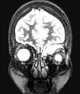

Primary orbital neoplasm

Eye neoplasms can affect all parts of the eye, and can be a benign tumor or a malignant tumor (cancer). Eye cancers can be primary (starts within the eye) or metastatic cancer (spread to the eye from another organ). [Source: Wikipedia ]